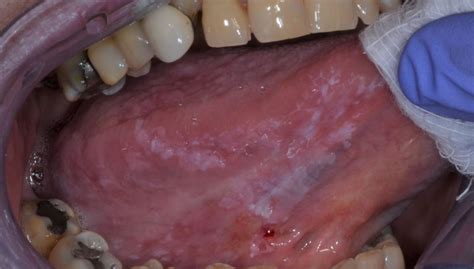

L'examen montre une ulcération irrégulière à bords épais ou parfois une lésion bourgeonnante. L'aspect de cette lésion, de taille variable, souvent située en regard d'un chicot dentaire, est suspect. La palpation de la lésion permet d'apprécierl'importance de l'infiltration et de l'induration caractéristique. Cette induration irrégulière dépasse les bords de l'ulcération et s'étend d'avant en arrière. Lereste de la langue est souple.

Le médecinrecherche une extension locale et des adénopathies (ganglions durs et parfois inflammés).La biopsie est indispensable pour porter le diagnostic.On recherche également un cancer associé des voies aérodigestives supérieures par une fibroscopie.